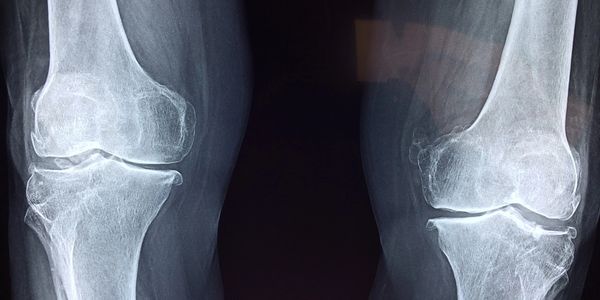

退化性關節炎、關節脫位、肌肉損傷、臂神經痛、血腫/水腫、足底筋膜炎、滑囊炎、臀部疼痛、肌腱炎、挫傷、下背痛、急慢性傷口